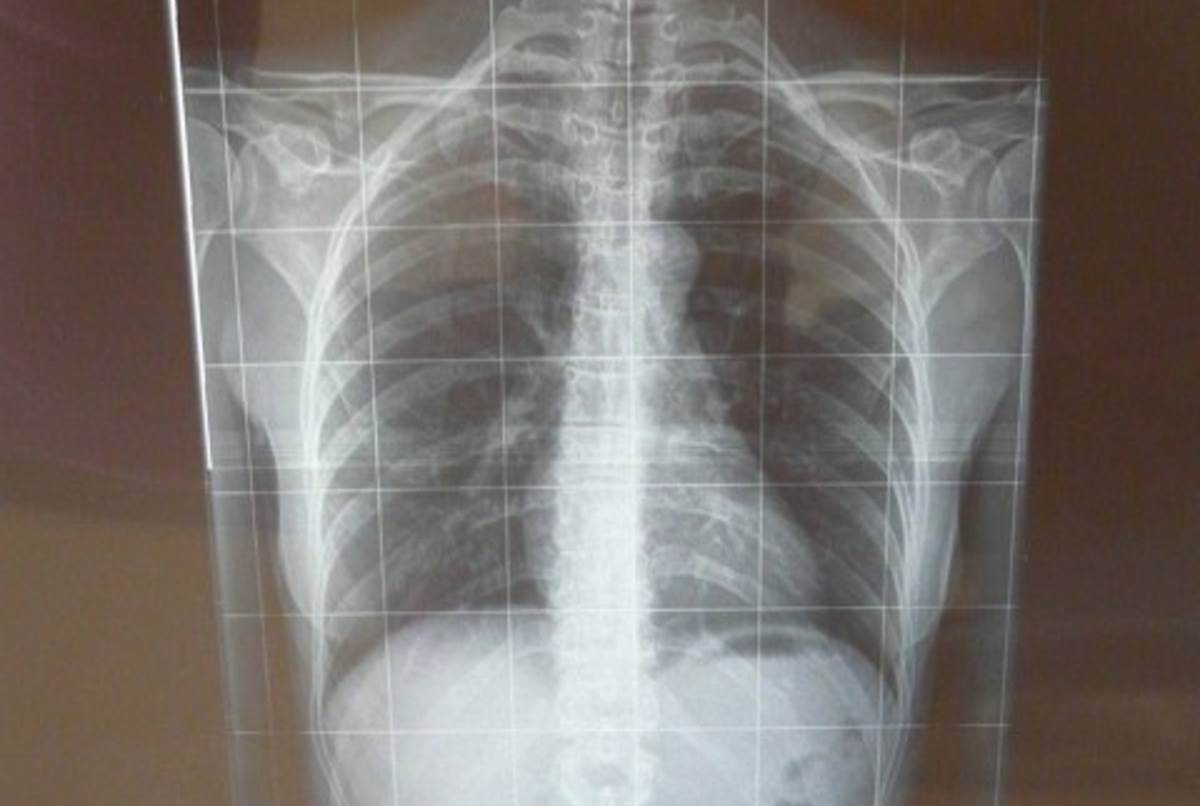

Сколиоз 7 градусов

Полный размер 1200 × 806 пикселей Как выглядит сколиоз